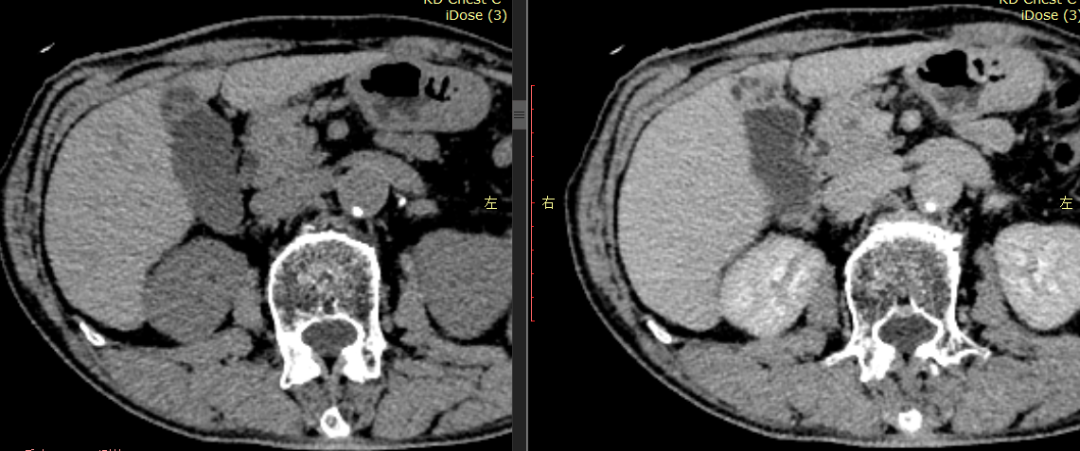

CASE 1